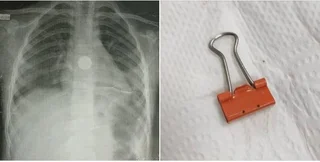

Туберкулез. Что нужно знать о болезни и почему важно вовремя обращаться к врачу

10 Март 2026 13:22 201 -